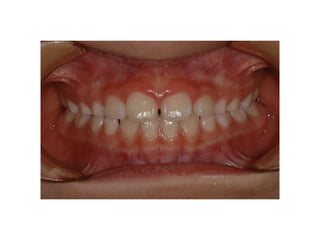

2009. 02.18.3y

2010.06.15 4y4m

2012 02 01

out of Tr 2yr